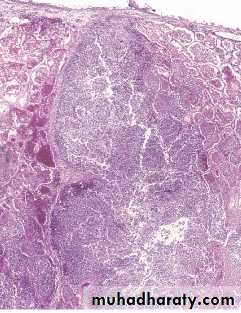

Morphology of Bronchiectasis

Usually affects lower lobes bilaterally (vertical airways).

Dilated airways up to four times of normal, reaching the pleura.

Tube-like enlargement (cylindroid) or fusiform (saccular).

Acute and chronic inflammation, extensive ulceration of lining epithelium with fibrosis.

Bronchiectasis